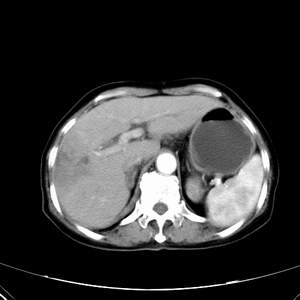

患者,女性,77岁,右上腹胀痛月余。afp正常。ca125升高。即往无肝炎病史。

肝右叶病灶是胆管细胞癌吗?门静脉右支癌栓形成?右侧肾上腺有问题吗?

最后5幅图片是延时7分钟的。门静脉右前支内有充缺吗?如有,肝血管瘤不好解释。

病灶渐进性向心性强化,延时病灶中心见条片状高密度影,局部见肝包膜回缩征,结合病人无肝炎病史,考虑肝右叶胆管细胞癌,门脉右支癌栓形成。